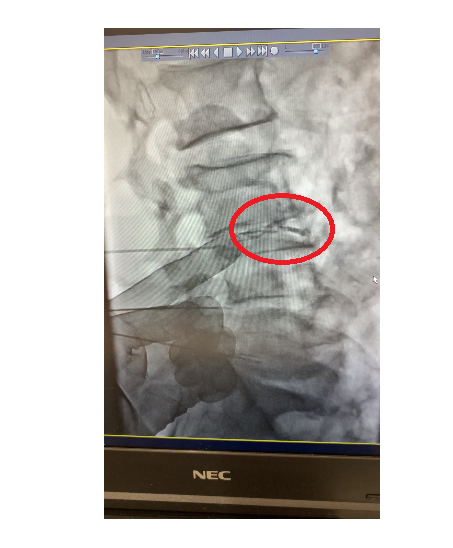

正在插入治疗用的穿刺针。骨头严重变形,通往椎间盘的路径有一定局限性,所以插入时尽量努力避开神经。

正在检查椎间盘破裂情况。确认后注入了修复再生药剂。治疗时间为16分。